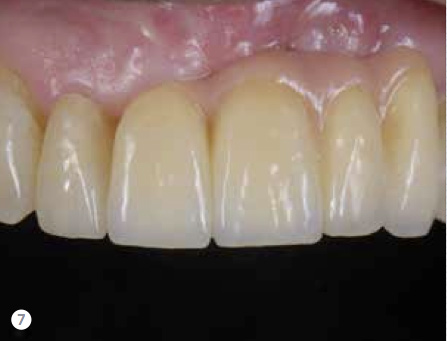

Fig 7. The patient’s mindset and his lip mobility played major roles in selecting from potential treatment redesign options.

Figure 7